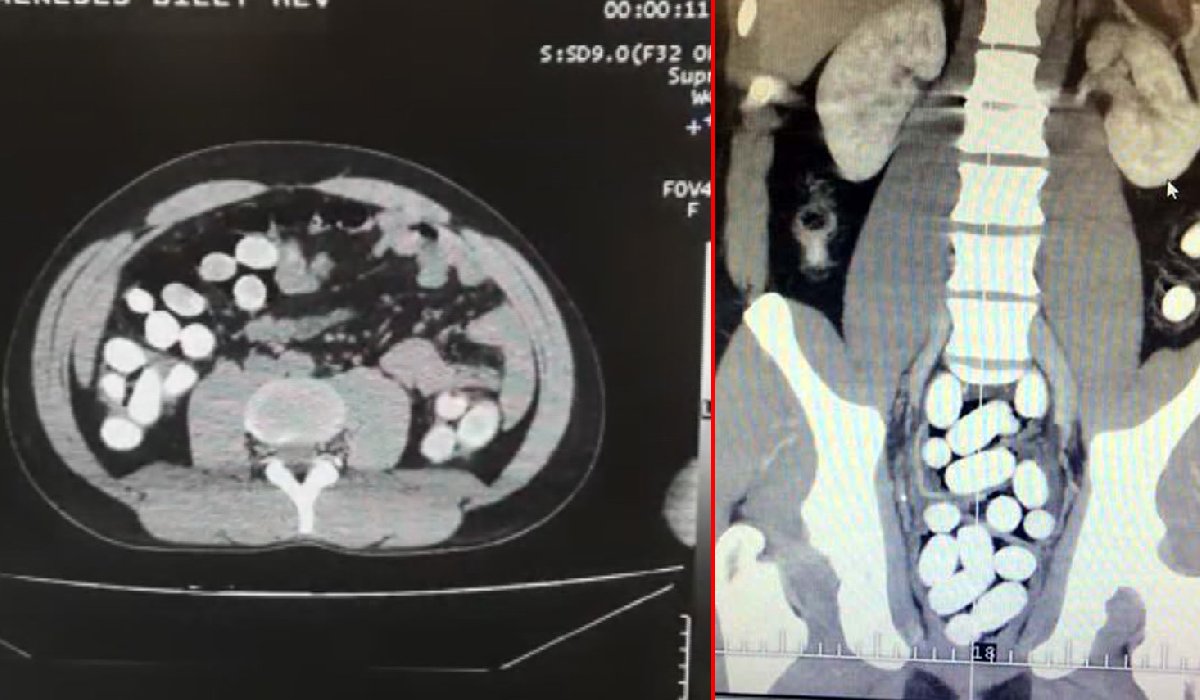

YUTUCU TESPİT CİHAZI İLE BULUNDUUyuşturucu kuryelerinin midelerinde olağan dışı bir sertlik tespit edilmesinin ardından, Gümrük Muhafaza ekipleri şüphelileri Türkiye'de sadece İstanbul Havalimanı'nda bulunan yutucu tespit cihazı ile kontrol etti. Bu cihazda şahısların midesinde şüpheli yoğunluk tespit edildi ve şahıslar muayene edilmek üzere hastaneye götürüldü. Burada yapılan tetkiklerde bir yolcunun midesinde 110 adet, diğer bir yolcuda 80 adet kapsül, bir diğer yolcuda da 24 adet şeffaf plastik bulunduğu tespit edildi.

KAPSÜLLERDEN UYUŞTURUCU ÇIKTIGümrük Muhafaza ekipleri, 2 kuryenin midesinden çıkan kapsüllerin içerisindeki toz maddeyi uyuşturucu test cihazı ile analiz etti. Analizin sonunda iki yolcunun midesinden çıkan tozun kokain olduğu anlaşıldı. Diğer yolcunun midesinden çıkan şeffaf plastikler içerisinde bulunan likit maddenin uyuşturucu test cihazı ile yapılan analizinde sıvı kokain olduğu anlaşıldı.